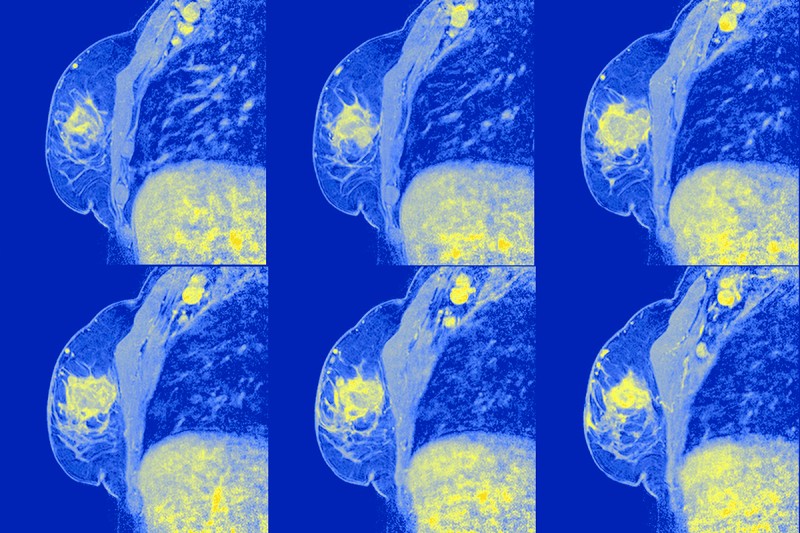

Patients with early-stage, node-positive breast cancer whose nodes are pathologically tumor-free (ypN0) after neoadjuvant chemotherapy may safely skip post-mastectomy nodal irradiation without increasing the risk of invasive breast cancer recurrence or death, according to results from a clinical trial published recently in The New England Journal of Medicine.  (1)

The B-51 trial evaluated whether regional nodal irradiation after a mastectomy or a lumpectomy improved outcomes in patients with stage T1 to T3, N1, and M0 node-positive breast cancer that converted to being node-negative after neoadjuvant chemotherapy. There were no significant differences between groups in five-year oncologic outcomes, including the interval to any invasive recurrence, as well disease-free survival (DFS) or overall survival (OS).  (1)